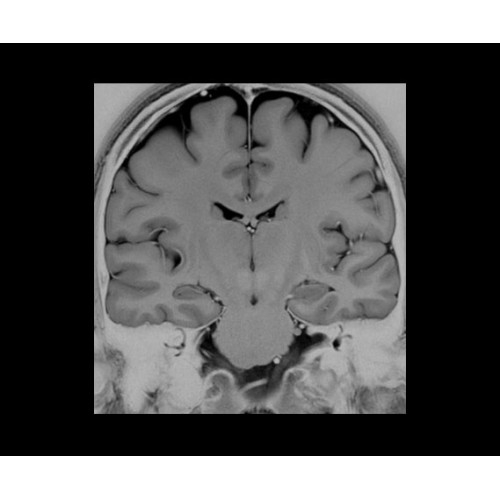

Поле обзора 50x50x50 см и апертура шириной 70 см позволят достоверно визуализировать сложные анатомические области для пациентов с крупным телосложением, например, плечи и бедра. Феноменальная однородность системы SIGNA Architect обеспечивает наиболее широкое поле обзора с улучшенными характеристиками градиентов. Ничто не останется незамеченным.

• NeuroWorks — универсальное решение для визуализации анатомии головного мозга, позвоночника, сосудов и периферических нервов с четкой дифференциацией тканей.

• 48-канальная катушка TDI для головы, входящая в базовую комплектацию SIGNA Architect, обеспечивает феноменальную производительность с учетом особенностей каждого пациента. Благодаря гибкому и универсальному дизайну, высокому соотношению сигнал/шум и передовым технологиям визуализации, таким как HyperWorks, учитываются потребности подавляющего большинства пациентов.